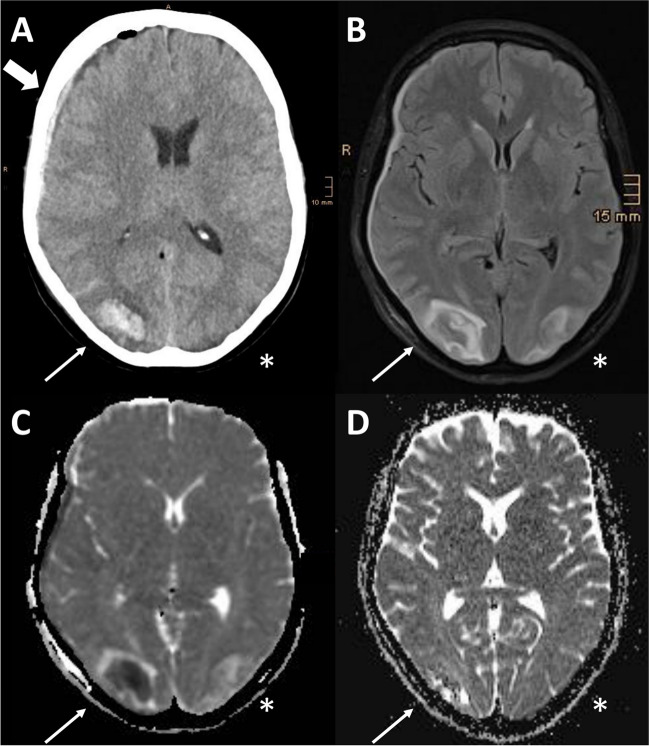

Fig. 2.

Imaging findings in our case of PRES after metronidazole administration. Native brain CT imaging showed A) right-sided occipital intracerebral haemorrhage with peripheral oedema (thin arrow), subdural bleeding (large arrow); left-sided grey-white matter junction oedema (*). MRI performed 2 days after clinical onset revealed bilateral occipital B) FLAIR (thin arrow and *) and C) ADC hyperintensities (thin arrow and *) indicating vasogenic edema. The relative right occipital hypointensity on the ADC map is related to the haemorrhage. D) Follow-up MRI after 2 months from clinical onset showed in the ADC map almost complete resolution of the vasogenic oedema and subtotal resorption of parenchymal haemorrhage (thin arrow and *). Abbrevations. ADC: apparent diffusion coefficient; CT: computed tomography; FLAIR: fluid-attenuated inversion recovery; MRI: magnetic resonance imaging; PRES: posterior reversible encephalopathy syndrome

After progressive improvement, the patient was discharged 13 days after the onset of PRES without hemianopia or other neurological sequelae, except for the unchanged right facial palsy. Follow-up MRI at approximately 2 months showed almost complete radiological recovery with resolution of the vasogenic oedema and subtotal resorption of parenchymal haemorrhage (Fig. 2D).

Two days after successful surgery, the patient complained of abdominal pain and diarrhea. Microbiological testing revealed positive stool samples for Clostridium difficile, for which metronidazole (400 mg × 3/day) was administered. One day after starting metronidazole, the patient developed a diffuse mild headache (numerical rating scale 4/10), dizziness and nausea, followed by altered mental status with somnolence. Neurological examination revealed left-sided homonymous hemianopia without further focal deficits. BP was modestly elevated at clinical onset (158/60 mmHg). Computed tomography (CT) revealed a right occipital intracerebral haemorrhage with peripheral oedema, right subdural and subarachnoid bleeding (Fig. 2A) as well as contralateral grey-white matter junction oedema. Laboratory parameters indicated a mild inflammatory reaction (Supplementary Table 1). Renal function was unremarkable [glomerular filtration rate, GFR > 90 ml/min (normal range > 60), creatinine 62 micromol/L (normal range 44–809) and electrolytes [Na+ 144 mmol/l (normal range 136–145), K+ 4.0 mmol/l (normal range 3.4–4.5), Ca++ 2.19 mmol/l (normal range 2.15–2.50), Cl− 107 (normal range 98–107)]. The patient was therefore admitted to the neurological intensive care unit (ICU) and the arterial hypertension was treated with continuous administration of urapidil and nimodipine. Over the next days, BP values remained normal without the need for intravenous antihypertensive medication. Headache was treated with metamizole and fentanyl transdermal patch. Magnetic resonance imaging (MRI), performed one day after symptom onset, showed subcortical T2, fluid-attenuated inversion recovery (FLAIR) and apparent diffusion coefficient (ADC) hyperintensities in occipital areas (Fig. 2B-C) without diffusion restriction signals reflecting vasogenic oedema (Supplementary Fig. 1). MRI including T2* gradient-echo sequences did not reveal findings associated with cerebral amyloid angiopathy [9]. Based on clinical and radiological findings, the diagnosis of PRES was made [1]. Given the previous association between PRES and metronidazole administration reported in the literature [10–12], metronidazole was discontinued 3 days after first administration and replaced by vancomycin (125 mg × 4/die). Neurofilament light chain protein (NfL) was measured in serum using the ELLA technology as previously described [13]. Serum NfL was massively elevated two days after symptom onset (166 pg/ml, normal values < 35 pg/ml according to our in-house reference values). Within 2 days of discontinuing metronidazole, the patient showed rapid clinical improvement with reduction of headache and improvement of mental status. At follow-up (4 days after symptom onset) serum NfL concentration were further increased (433 pg/ml).